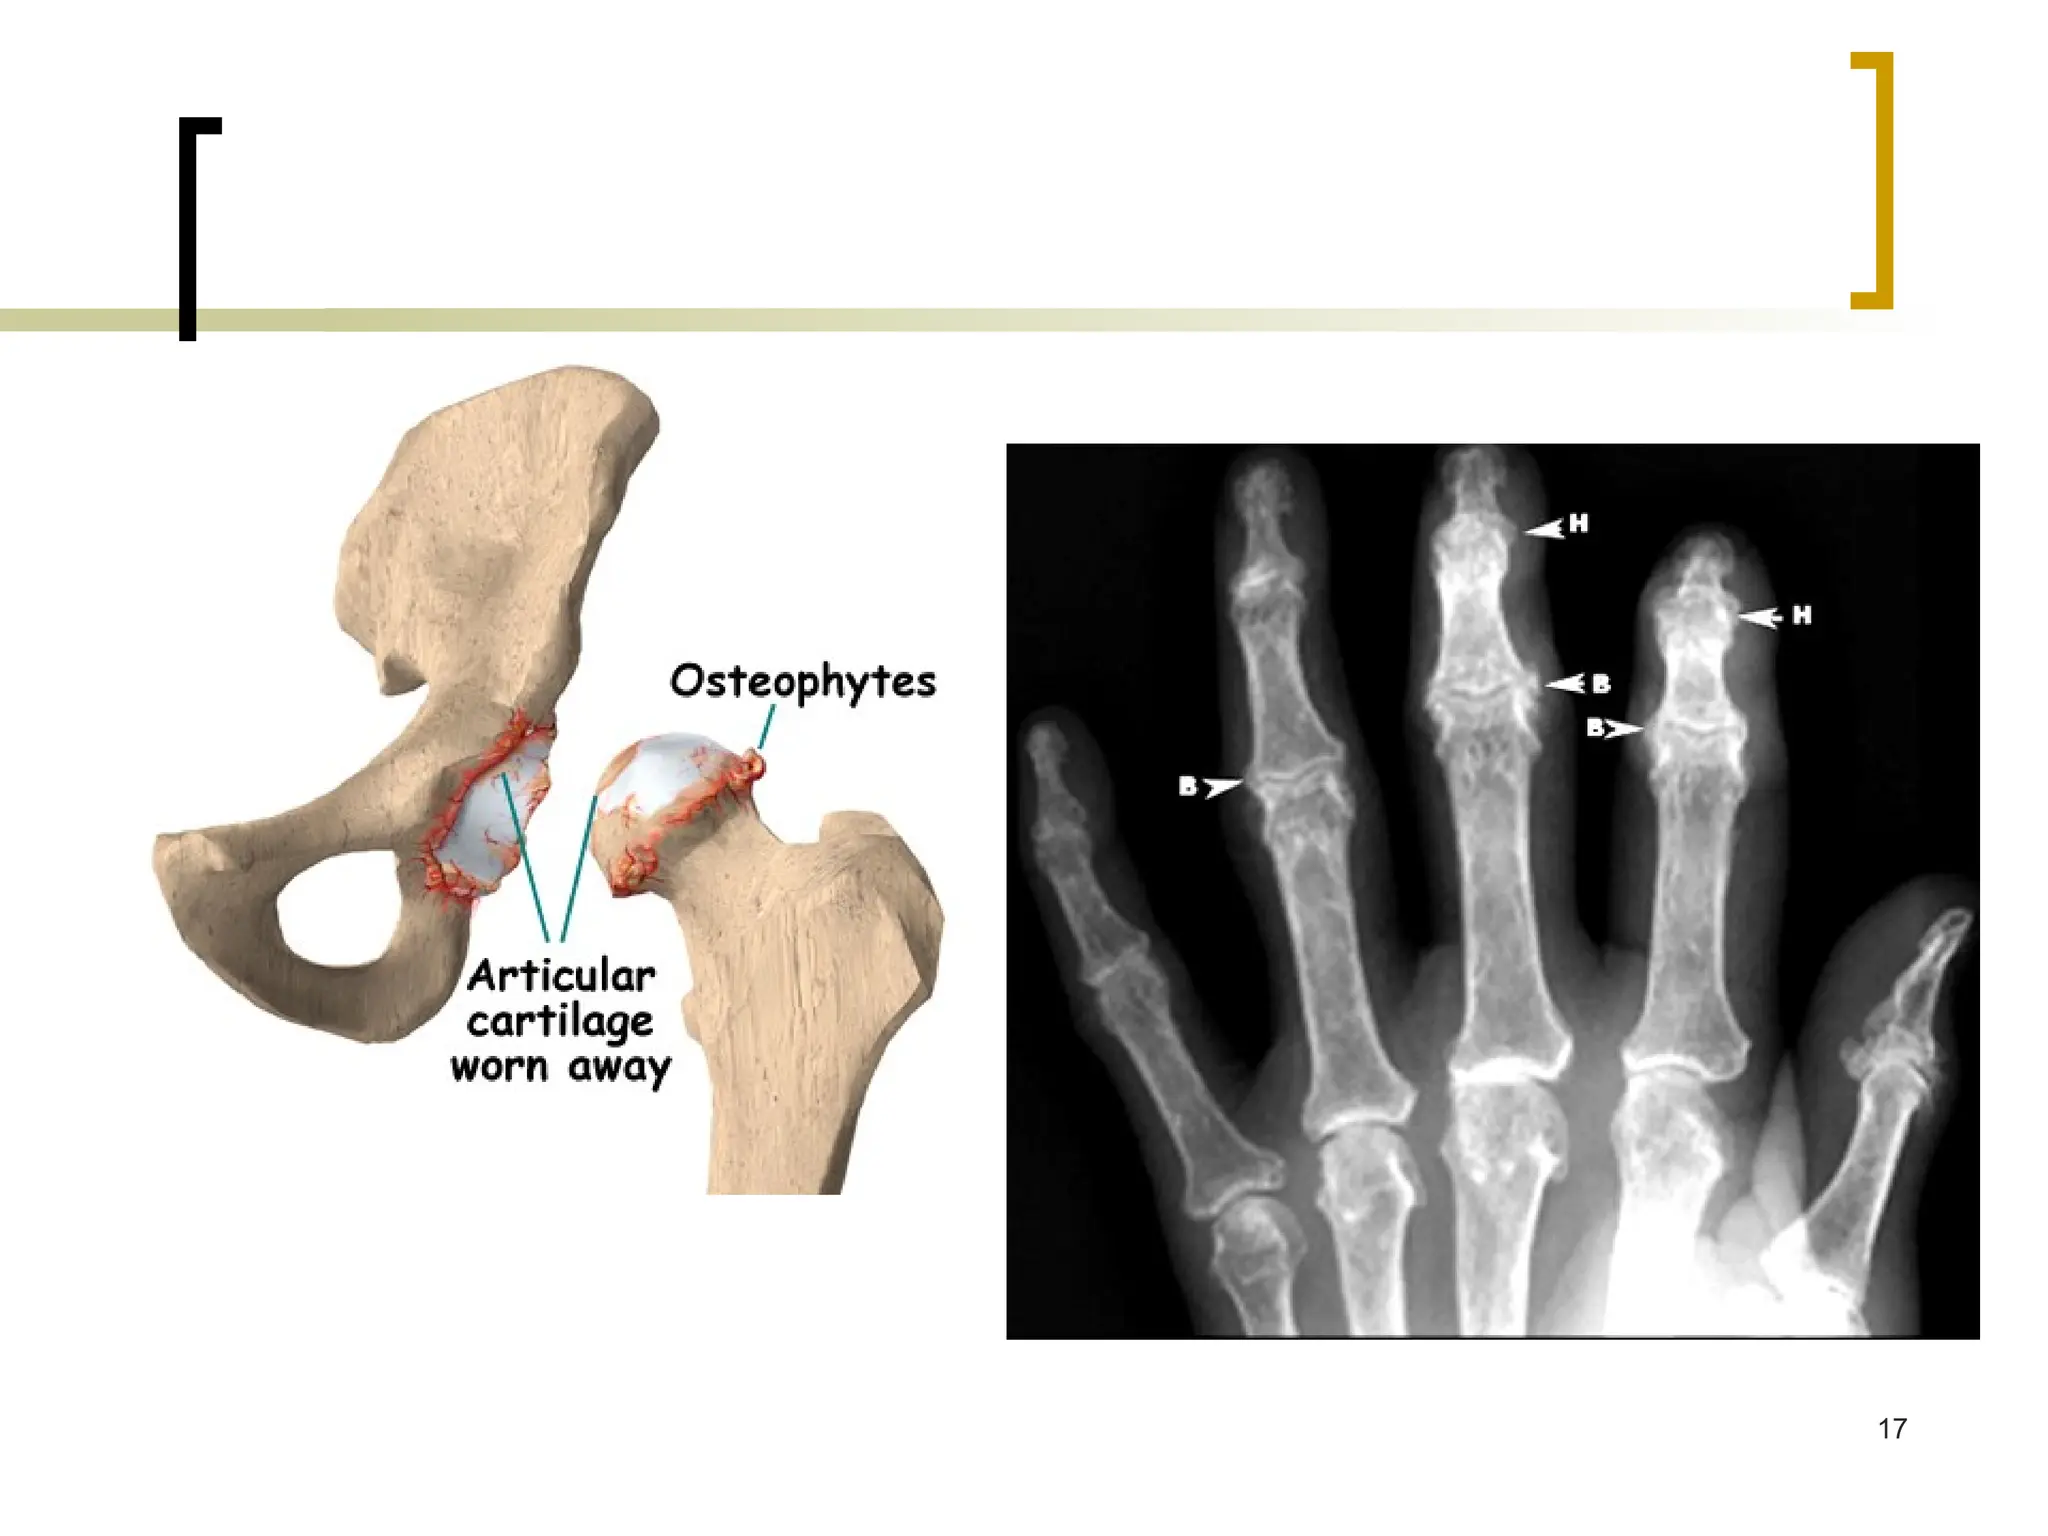

PATHOPHYSIOLOGY

 OA is a multifactorial disease typified by:

 progressive destruction of joint cartilage,

 erratic new bone formation,

 thickening of subchondral bone and the

joint capsule,

 bony remodeling,

 development of osteophytes,

 variable degrees of mild synovitis, and

other changes.

Cartilage in OA (cont’d)

 Subchondral bone undergoes pathologic changes that may

precede, coincide with, or follow damage to the articular cartilage

 In OA, subchondral bone releases vasoactive peptides & MMPs

 Neovascularization & subsequent ↑ permeability → further

cartilage loss

 → joint space narrowing & painful, deformed joint

 the remaining cartilage softens & develops fibrillations (vertical

clefts into the cartilage), with splitting & exposure of underlying

bone

 → cartilage is eroded completely → subchondral bone becomes

dense, smooth (eburnation) →

 ↓ weight-bearing ability & microfractures →

 new bone formations, or osteophytes

16

17

 There is evidence that osteophytes can help stabilize

osteoarthritic joints

Manifestations of inflammatory OA:

Heberden nodes (distal interphalangeal joint) noted on all fingers

Bouchard nodes (proximal interphalangeal joint) noted on most

fingers.

Heberden's nodes

(osteophytes)